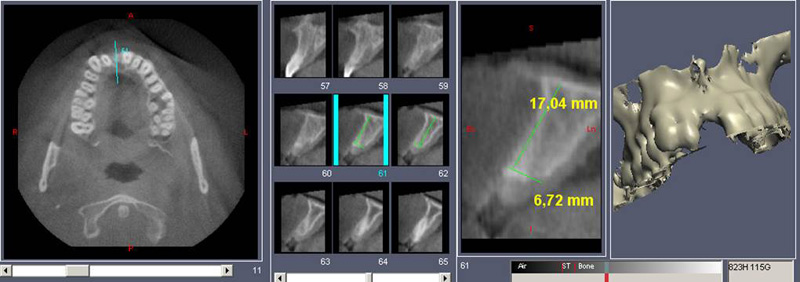

V případě chybění většího počtu zubů v postranních úsecích čelistí je možné ošetření pomocí implantátů, které nahradí ošetření pomocí snímacích náhrad kotvených na zbývajících zubech nebo patře.

Podmínkou je opět dostatečné množství kosti.

Protetické řešení může být pomocí můstku, který je kotvený na implantátech nebo pomocí jednotlivých korunek na implantátech.